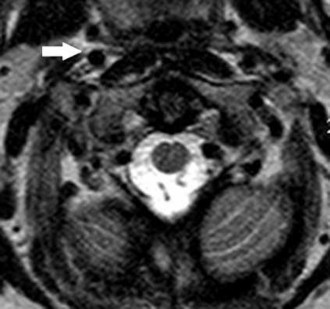

A 22-year-old man sustains an injury to his right knee in a motor vehicle collision. Figure 22a is the posterior stress radiograph of the involved knee, and Figure 22b is a selected MR image that identifies the injured structure.

CLINICAL SITUATION FOR QUESTIONS 22 THROUGH 25

Which relationship is noted for the structure identified by the arrow in Figure 22b? 24

The stress radiographs demonstrate posterior instability of the right knee in flexion. The MR images demonstrate injury to both the anterior and posterior cruciate ligament (PCL), with the stump identified with the arrow on the MR image (Figure 22b). The PCL has 2 functional bands. The anterolateral bundle originates from the roof of the intercondylar notch. It runs in a posterolateral direction onto the tibial crest between the posterior attachment of the medial and lateral menisci. During a double-bundled posterior ligament reconstruction, the

anterolateral bundle is tensioned with the knee in a position of mid flexion. The posteromedial bundle has a variable pattern of tension both in extension and in high flexion. Tensioning of the posteromedial bundle in extension may contribute to resistance against knee hyperextension.

The meniscofemoral ligaments are variably present. Although 93% of knees have been reported to have at least 1 meniscofemoral ligament present, both ligaments are simultaneously present in approximately 50% of knees. The ligament of Humphrey (anterior meniscofemoral ligament) and ligament of Wrisberg (posterior meniscofemoral ligament) are delineated by their anatomic relationship to the posterior cruciate.